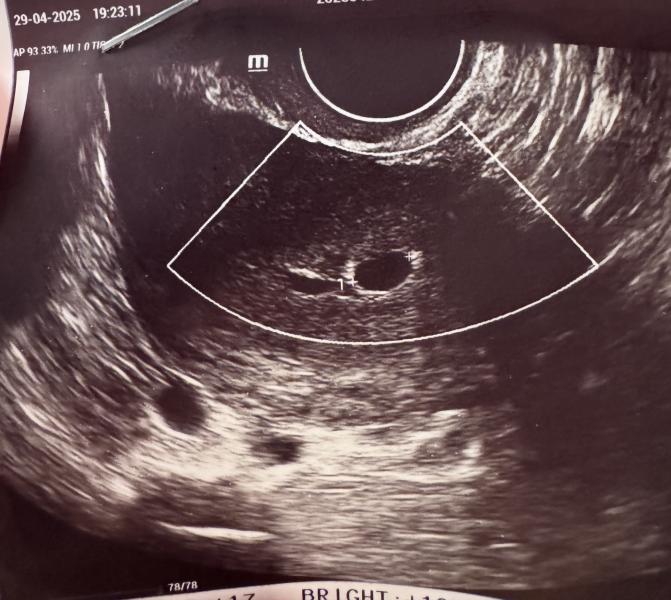

Девочки, лежу на узи, сначала абдоминально смотрит, и говорит чет не то, надо вагинально, я говорю а что? Что то не так? Она такая да нет, просто кажется 2 плода, срок 4 недели, и пока непонятно, типа приходите через 1,5-2 недели, там точно посмотрим, а так четко видно второе плодное яйцо типа 👀👀👀че думаете? Это реально? Я просто в шоке сейчас